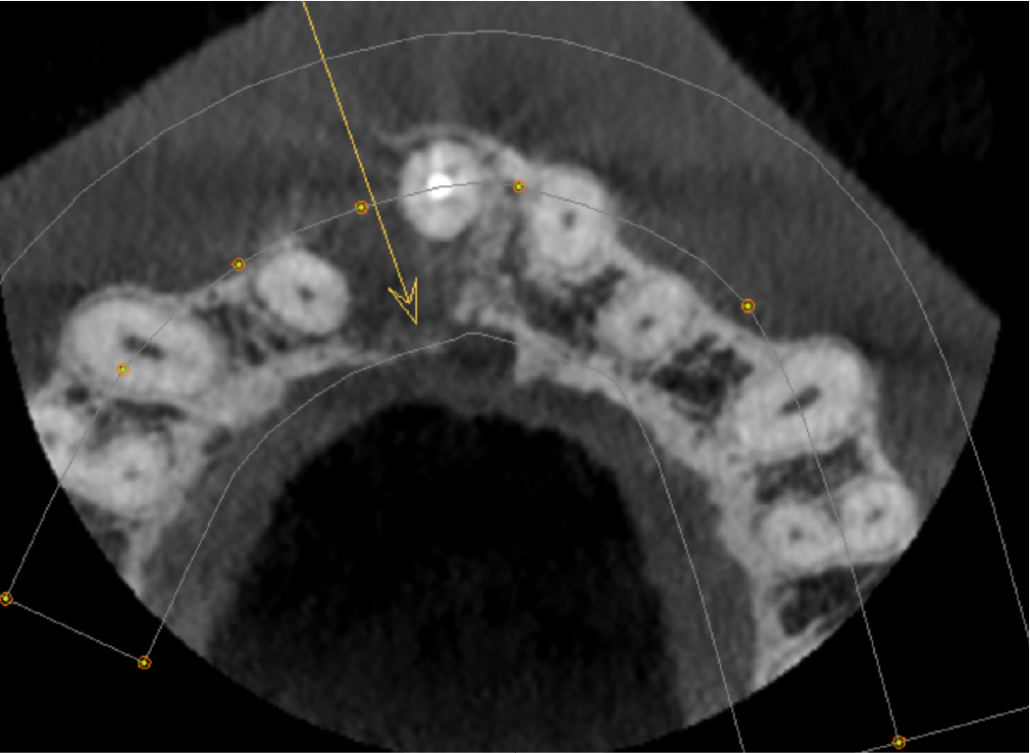

Axial view showing the palatal cortex eroded at the level of the oral entrance to the nasopalatine canal (arrow)

The UR1 is root filled with a small amount of extruded filling material inside the lesion. There is a well-defined, unilocular radiolucency measuring 12mm, extending from the UR1 apical region to the UR2 apex. The origin is probably from the apex of the UL1. The buccal cortex is expanded and perforated. The palatal cortex is eroded at the level of the oral opening of the nasopalatine canal. The lesion has not eroded the nasopalatine canal more superiorly. The appearance is that of a radicular cyst.